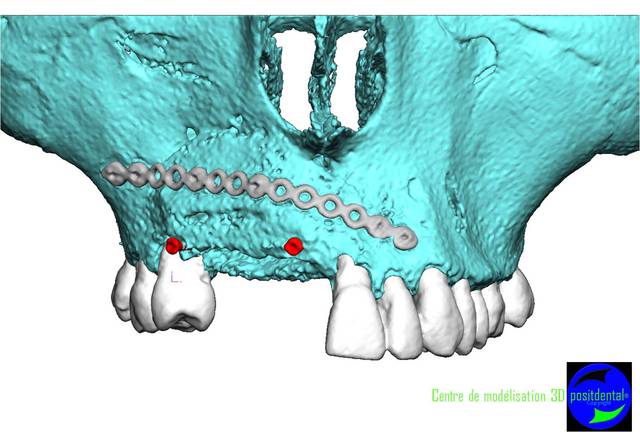

Perte d un greffon iliaque

Retraité en basale voici 6 ans avec succès